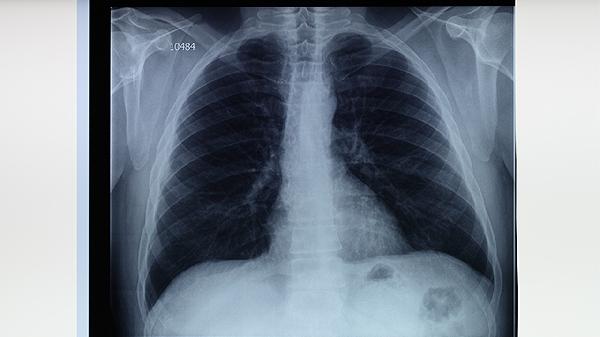

3、诊断方法

结核菌素皮肤试验和干扰素释放试验可用于筛查。胸部X线检查能发现肺部病变,痰涂片找抗酸杆菌和痰培养是确诊依据。分子生物学检测如GeneXpert可快速诊断耐药结核。